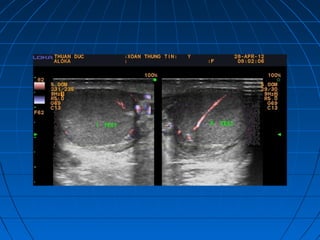

Hẹp phì đại môn vịHẹp phì đại môn vị

(tăng sinh mạch máu)(tăng sinh mạch máu)

 Tiêu chuẩn hình thái học: môn vị phìTiêu chuẩn hình thái học: môn vị phì

đại nằm kéo dài , hình cocard trênđại nằm kéo dài , hình cocard trên

nhát cắt ngang, tăng sinh mạch máunhát cắt ngang, tăng sinh mạch máu

trong cơtrong cơ